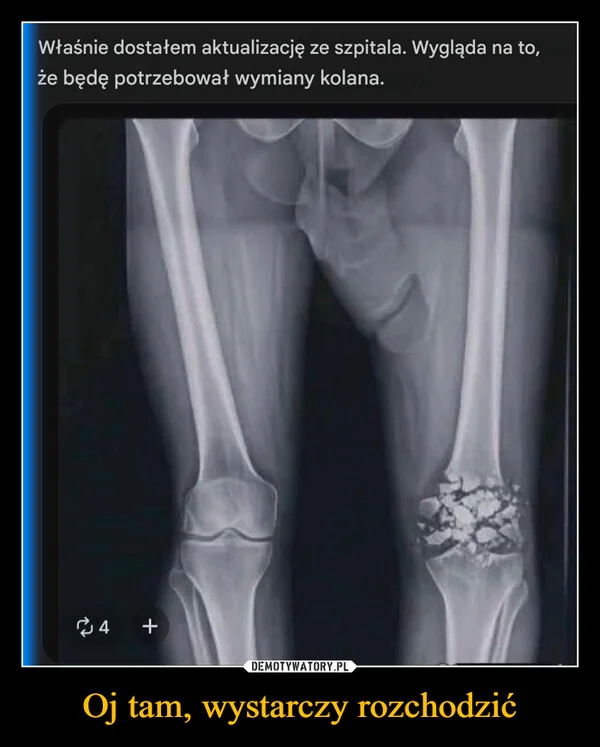

Oj tam, wystarczy rozchodzić